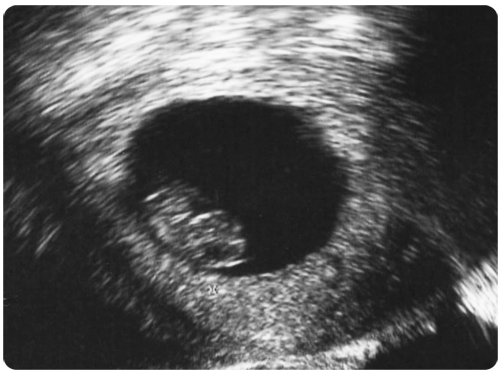

A blood pregnancy test is scheduled two weeks after the embryo transfer. If the test is positive, an ultrasound examination is scheduled two weeks later to visualize the implantation site and check for a heartbeat within the embryo. Once a heartbeat is detected, there is a 95% probability that the pregnancy will result in a live birth.

This ultrasound picture shows a six-week pregnancy. The pregnancy sac is 25 mm in diameter. The baby inside the sac is only 13 mm long. It is already possible to distinguish the baby’s head and body and to see the cardiac activity.